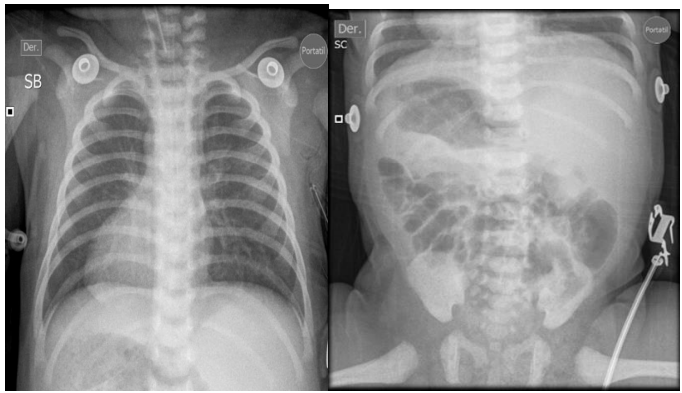

Newborn female referred from San Vicente de Paul Hospital for respiratory distress syndrome and suspected congenital heart disease, this is a 1 day old newborn, the result of the fifth pregnancy, a 41 year old mother, 39 weeks gestation, Grava 5, 2 stillbirths, prenatal check-ups number 5, blood type O positive, mother has gestational diabetes, perinatal screening: HIV negative, VDRL non-reactive, Hepatitis B negative, Toxoplasma IGG positive and IGM negative, delivered by cesarean section due to iterative, born with the following anthropometric parameters: weight 3520 grams, height 50 cm, head circumference 36 cm, chest circumference 35 cm. Spontaneous neonatal adaptation, Apgar 8 - 10 - 10, at birth the baby develops respiratory distress syndrome with a 3-point Silverman - Anderson score, for which reason they are transferred to the newborn unit, non-invasive ventilation is started, a chest x-ray is taken where dextrocardia is evident, for which reason they are referred to the UROS Clinic for comprehensive management in the neonatal intensive care unit. On admission, the patient was hemodynamically stable and showed no signs of low output. He received noninvasive ventilatory support with a high-flow nasal cannula, a FIO2 of 35%, with saturation at target levels. However, during hospitalization, the patient's respiratory condition deteriorated with increased effort, increased retraction, and thoracoabdominal dissociation. Therefore, orotracheal intubation was performed with a 3.5 tube, which was 10 cm from the commissure. Ventilation parameters were adjusted. The patient's progress was favorable. Venous blood gases were taken and showed a pH of 7.32, PO2 35, PCO2 43, HCO3 22, BE -3.9, and lactate of 4.1 with normal serum electrolytes. A chest x-ray was taken and showed a cardiac silhouette on the right and a liver on the left. He ventilated 9 intercostal spaces. without opacities, diagnosis situs inversus totalis , hemodynamically well perfused without low output with blood pressure and heart rate at goals, without indication of inotropic support, heart sounds audible on the right. pulses present. Complementary studies are performed CENTRAL NERVOUS SYSTEM ULTRASOUND study within normal limits, TOTAL ABDOMEN ULTRASOUND An alteration in the position of the abdominal organs is striking, observing the spleen in the right hypochondrium and the liver in the left hypochondrium. Liver of normal shape, size and echogenicity, without focal or diffuse lesions in its parenchyma. Gallbladder and bile duct without alterations. Kidneys, spleen, pancreas and retroperitoneum of normal ultrasound appearance. Empty bladder which prevents assessment of pelvic organs. No masses, collections or free fluid are identified in the abdominal cavity. OPINION: ALTERATION IN THE POSITION OF ABDOMINAL ORGANS (SPLEEN AND LIVER) AN ECHOCARDIOGRAM IS SUGGESTED TO RULE OUT DEXTROCARDIA, ECHOCARDIOGRAM by pediatric cardiology showing CONSERVED SYSTODIASTOLIC FUNCTION OF THE LEFT VENTRICLE TAPSE 9 MM TRICUSPID AND PULMONARY FAILURE PHYSIOLOGICAL OVALE FOSSA 4.1 MM PSPE 34.7 MMHG RESTRICTIVE DUCTUS TOWARDS CLOSURE, DEXTROCARDIA, multidisciplinary evaluations are performed GENETICS patient in stable general condition situs inversus totalis is an alteration that occurs in about 1:10,000 people, with a higher prevalence in men than in women. It is important to rule out whether this occurs in isolation or as part of a more complex syndrome. It is important to keep in mind that 80% of patients have heart disease, which is why a transthoracic echo is required to rule out any anomaly of this type. Additionally, it is important to rule out primary ciliary dyskinesia due to the history of respiratory failure reported by the service. A karyotype with G banding is requested, genomic hybridization is requested (study of deletions and duplications) PEDIATRIC NEUROLOGY patient with high neurological risk due to congenital malformation, with neurological examination with deficit for gestational age, weak suction for gestational age, with echo of the central nervous system without pathological alterations, I request a CEREBRAL MRI Clinical information: situs inversus. Findings: The myelination pattern is normal for the age. The signal from the brain parenchyma does not show alterations. Gray nuclei of the base and thalami without alterations. Subarachnoid space and ventricular system within normal limits for the age. Hypothalamic-pituitary axis, pineal region and corpus callosum of normal appearance. Structures of the posterior fossa without findings of pathological value. Preserved craniovertebral junction. Significant bilateral Oto mastoid occupation. Mucosal thickening in the pneumatized paranasal cavities. Conclusion: Significant bilateral Otomastoid occupation . Intracranial structures within normal limits for age. PEDIATRIC PULMONOLOGY chest x-ray situs inversus, without air leak, adequate lung expansion, OTORHINOLARYNGOLOGY patient with suspected immotile cilia syndrome, currently stable, an electron microscopy of the nasal mucosa is ordered, which can be performed on an outpatient basis, should continue with periodic check-ups by otorhinolaryngology, PEDIATRIC OPHTHALMOLOGY patient with no alterations in the ophthalmological examination, is considered within normal parameters. Control in 6 months , PEDIATRIC CARDIOLOGY newborn with dx of total situs inversus , the echocardiogram showed a systolic pulmonary pressure of 35 mmHg and a restrictive ductus, heart in dextrocardia without dyspnea or cyanosis, finally the patient shows favorable evolution, it is possible to withdraw respiratory support, outpatient follow-up is ordered by different specialties.

Figure 1. Complete chest-abdomen situs inversus radiograph. Cardiac apex on the right. Liver in the left hypochondrium and gastric fundus in the right hypochondrium.